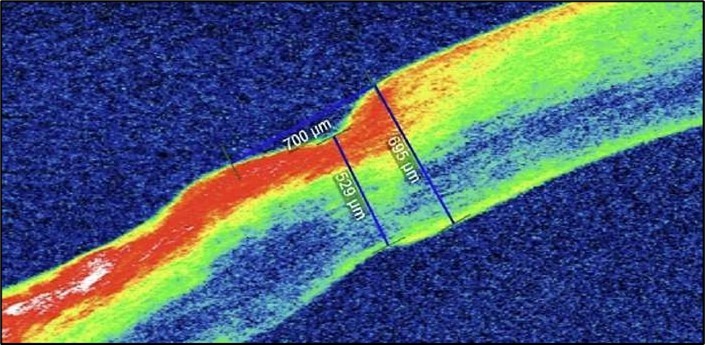

On the current presentation, Snellen VA was 6/6 in the right eye and 6/9 in the left eye, with normal IOP. The left eye demonstrated mild upper lid edema and intense nasal ciliary injection. Slit-lamp evaluation revealed a crescentic area of stromal corneal melting between 7 and 10 o’clock nasally, with overhanging edges and a fluorescein-positive base. No corneal infiltrates were present, and the surrounding stroma remained clear. The anterior chamber was deep and quiet, lens was transparent, pupil was round and reactive & normal posterior segment. Anterior segment optical coherence tomography (AS-OCT) confirmed a localized ulcer, measuring 1324 µm in horizontal width and extending to a depth of 380 μm, compared with an adjacent healthy corneal thickness of 824 µm, corresponding to approximately 46.1% stromal thinning (Figure 1a, Figure 1b, Figure 1c)

Serial anterior segment OCT was employed throughout treatment to monitor corneal changes and response to interventions. Figure 7a, Figure 7b, Figure 7c, Figure 7d illustrate the ulcer’s progression: initial severity, minimal early response to medical therapy, post-operative healing after conjunctival resection, and sustained recovery at six-month follow-up.

Figure 7a.(At presentation): AS-OCT reveals a crescent-shaped peripheral corneal ulcer with marked stromal thinning of 380 µm in depth and complete loss of the overlying epithelium. The ulcer spans 1324 µm in width. The ulcer base appears concave with hyperreflective stromal margins, and a distinct overhanging edge is visible at the inner margin.

Figure 7b.(Following systemic immunosuppression): AS-OCT shows a reduction in ulcer depth to 338 µm and a narrower ulcer width of 1180 µm, suggesting minimal therapeutic response. The ulcer bed remains irregular with persistent stromal hyperreflectivity, likely due to ongoing inflammation. The overhanging edge is less prominent, and partial re-epithelialization is observed.